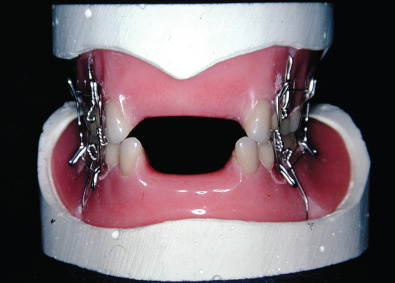

Historically, edentulous mandible fractures were treated by closed reduction. This required altering the patient’s denture and fixating the dental prostheses to the patient’s jaws and using postoperative maxillomandibular fixation (MMF). Alternatively, dental splints could be fabricated and secured to the patient and postoperative maxillomandibular fixation could be used. The dental splints could be one- or two-piece constructs. The one-piece constructed dental prosthesis is known as the Gunning splint. Treating edentulous mandible fractures with dental prostheses required additional knowledge not available to all surgeons managing facial fractures. A dental laboratory facility needed to be available in order to fabricate the acrylic prostheses after dental models had been obtained. This could be cumbersome, time-consuming and delay patient care. Additionally, the patient’s postoperative course was very difficult because of the dental appliances fixated to their jaws and the postoperative MMF. External fixators have also been used to stabilize edentulous mandible fractures as there are no teeth present. Precise anatomical reduction is often difficult with external fixators, especially in the atrophic mandible fracture with reduced bone stock. Management of edentulous mandible fractures by closed reduction techniques was difficult for the patient and had a high complication rate of nonunion ( Figs. 1.21.7–1.21.11 ).